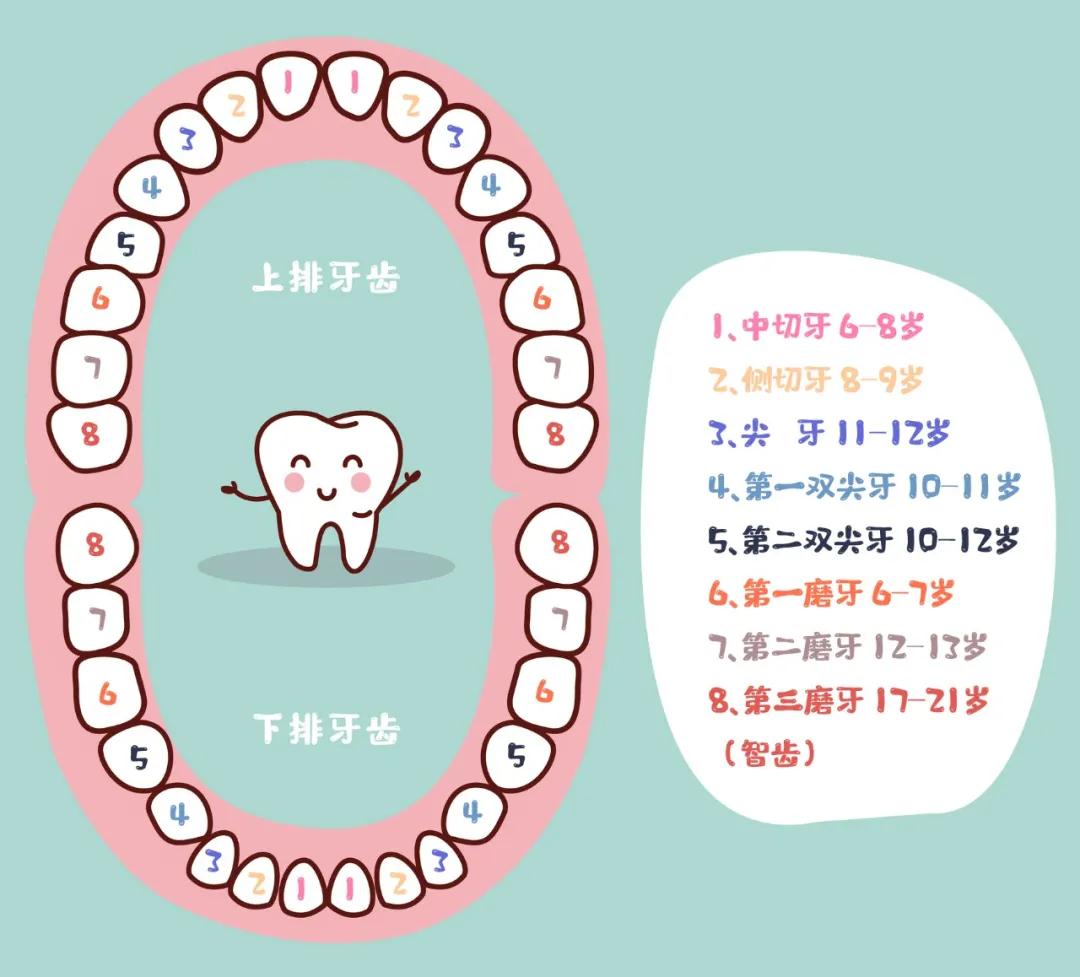

宝宝正常换牙时间是在6岁左右,最早在4岁,最晚大概在7岁,如果只是提前、或推迟一两年换牙,并不会给孩子健康带来影响。